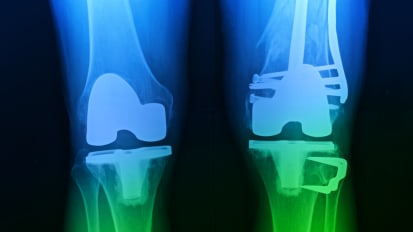

Sickle cell patients face higher risks in joint reconstruction surgeries News

Sickle cell patients face higher risks in joint reconstruction surgeries

Patients with sickle cell disease (SCD) who undergo total knee replacement are at higher risk for complications than non-SCD patients, according to a large-scale, retrospective study by researchers from UT Southwestern Medical Center and the University of Calgary.